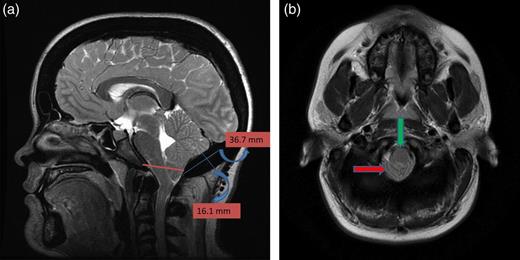

A 25-year-old female patient presented with 1-year history of occipital headache. The headache was increasing with coughing, sneezing and bending over. She had also complaints of intermittent bilateral hand numbness and bilateral feet burning. She was evaluated with magnetic resonance imaging (MRI), which showed Chiari I malformation with a 7 mm descent of cerebellar tonsils (Fig. 1 a and b). Computed tomography demonstrated diffuse calvarial thickening and loss of the medullary space (Fig. 2). Her past medical history was consistent with left eye surgery due to amblyopia when she was a child and she was blind in her left eye. Radioactive 131I treatment had been given due to the Graves’ disease and hyperthyroidism; therefore, she was hypothyroidic and was using levothyroxine daily. Her mother also was operated on because of the Chiari malformation. She had four siblings, and they did not have any pertinent medical history. Her physical examination revealed prominent occipital area and midfacial hypoplasia. Increased cortical thickness in her long bones was also demonstrated (Fig. 3 a–c). There were no abnormal findings on neurological examination except of left eye amorozis. The patient underwent surgery for decompression of posterior fossa. Large enough posterior fossa craniectomy with C1 laminectomy was performed with SSEP and MEP monitoring. Dura was opened in ‘Y’ shape, and duraplasty was performed with the pericranium. Arachnoid was kept intact. Her headaches improved significantly in postoperative period. She developed superficial wound infection, which was treated with simple washout and antibiotics.

(a) Sagittal T2-weighted image showing cerebellar tonsillar herniation and diffuse thickening of the occipital bone. (b) Axial T1-weighted image showing compression on the upper cervical spinal cord (green arrow) and cerebellar tonsillar herniation (red arrow).

This case is the second ADO case associated with Chiari type I, which presented with hindbrain headache and numbness on the upper extremity without other cranial nerve compression sign. MRI revealed brain stem compression, tonsillar herniation, occipital bone thickening and shallow posterior fossa. The first diagnosis was Chiari type I, but detailed history, endocrinologic and radiologic work-up yielded as an ADO, which was a final diagnosis.